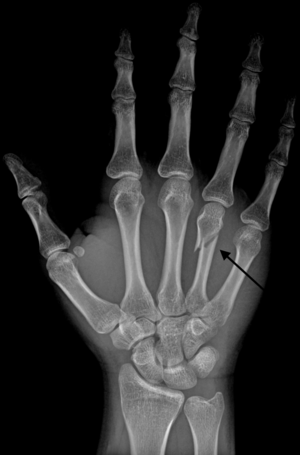

Boxer's Fracture is a colloquial term for a fracture of one of the metacarpal bones of the hand. Classically, the fracture occurs transversely across the neck of the bone, after the patient strikes an object with a closed fist. Alternate terms include scrapper's fracture or bar room fracture.

As these are colloquial terms, texts and medical dictionaries do not universally agree on precise meanings. Various authorities state that a "Boxer's fracture" means a break in specifically the second metacarpal bone or third metacarpal bone,[1] with "Bar Room fracture" being specific to the fourth metacarpal bone or fifth metacarpal bone.[2] Though some writers assert that Boxer's fracture and Bar Room fracture are distinct terms representing injuries to different bones, this distinction seems to have been lost over time and most medical professionals now describe any metacarpal fracture as a "Boxer's Fracture" .

Diagnosis by a doctor’s examination is the most common, often confirmed by x-rays. X-ray is used to display the fracture and the angulations of the fracture. A CT scan may be done in very rare cases to provide a more detailed picture.